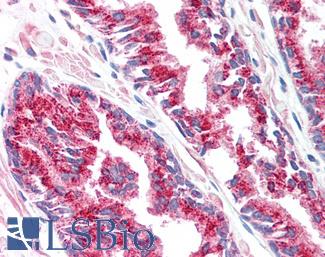

ERBB2 / HER2

Anti-ERBB2 / HER2 antibody IHC of human breast, carcinoma. Immunohistochemistry of formalin-fixed, paraffin-embedded tissue after heat-induced antigen retrieval. Antibody LS-B2133 concentration 5 ug/ml.